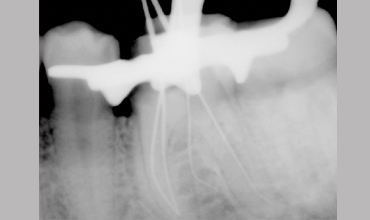

Management Of Radix

Management Of Radix Entomolaris In Mandibular First Molar